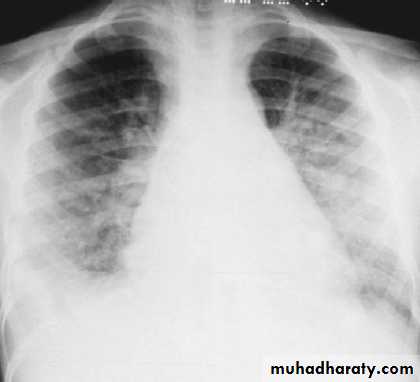

Respiratory distress, orthopnea, and cough may be symptoms of pulmonary edema and heart failure.

• CXR is indicated in those with signs of heart failure or respiratory distress.

CXR of a patient with poststreptococcal glomerulonephritis showing pulmonary edema